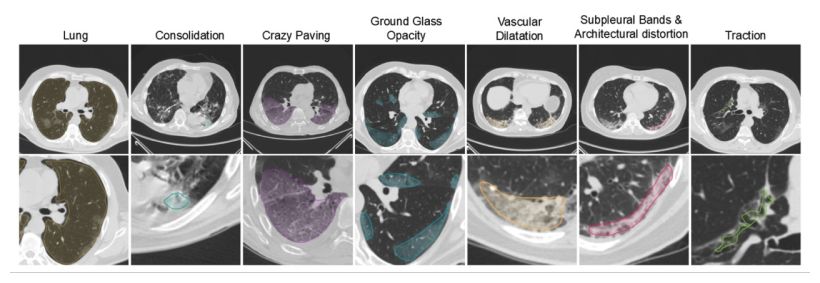

Η εφαρμογή της τεχνητής νοημοσύνης στη διαδικασία του triage (της διαλογής των ασθενών) μπορεί να συνδράμει στη βελτιστοποίηση των εσωτερικών νοσοκομειακών πόρων και της θεραπευτικής διαδικασίας του ασθενούς, η οποία θα λαμβάνει χώρα με την αναγκαία απομόνωση, ανάλογη του επιπέδου σοβαρότητας της λοίμωξης. Ο αλγόριθμος, θα μπορούσε να αναλύσει γρήγορα εικόνες υπολογιστικής τομογραφίας και έτσι να κατηγοριοποιήσει τους ασθενείς με COVID-19 σε τρεις ομάδες με κριτήριο την σοβαρότητα της νόσου: η πρώτη ομάδα περιλαμβάνει άτομα που μπορούν να συνεχίσουν την απομόνωση στο σπίτι, η δεύτερη ομάδα τους ασθενείς που χρήζουν νοσηλείας και η τρίτη ομάδα περιλαμβάνει τους πιο σοβαρά προσβεβλημένους ασθενείς. Οι τελευταίοι όντας εκείνοι που πρέπει να νοσηλευτούν έγκαιρα στην μονάδα εντατικής θεραπείας. Η μέθοδος θα μπορούσε να βελτιστοποιήσει τη διαχείριση του τεράστιου όγκου δεδομένων που παράγεται διαρκώς από τις νοσοκομειακές εγκαταστάσεις.

Η χρήση της τεχνητής νοημοσύνης στην διαγνωστική ανάλυση

Την μελέτη που δημοσιεύθηκε στο International Journal of Environmental Research and Public Health θα ακολουθήσει μια δεύτερη φάση δοκιμών και επικύρωσης του αλγορίθμου στην κλινική πρακτική. Η χρήση της τεχνητής νοημοσύνης, σε μια εποχή έκτακτης υγειονομικής κατάστασης όπως η τρέχουσα, θα μπορούσε να επιτρέψει μια ταχύτερη ανάλυση των διαγνωστικών εικόνων αποτελεσματικότερη από εκείνη ενός ειδικού. Επιπλέον, η έγκαιρη ταυτοποίηση του υψηλού ή χαμηλού κινδύνου του μεμονωμένου ασθενούς μπορεί να βοηθήσει στον εξορθολογισμό του τρόπου της διαχείρισης των θαλάμων και της φροντίδας των ασθενών νωρίτερα από τα αποτελέσματα των κλινικών ή εργαστηριακών εξετάσεων, για τα οποία ο χρόνος αναμονής είναι μεγαλύτερος.